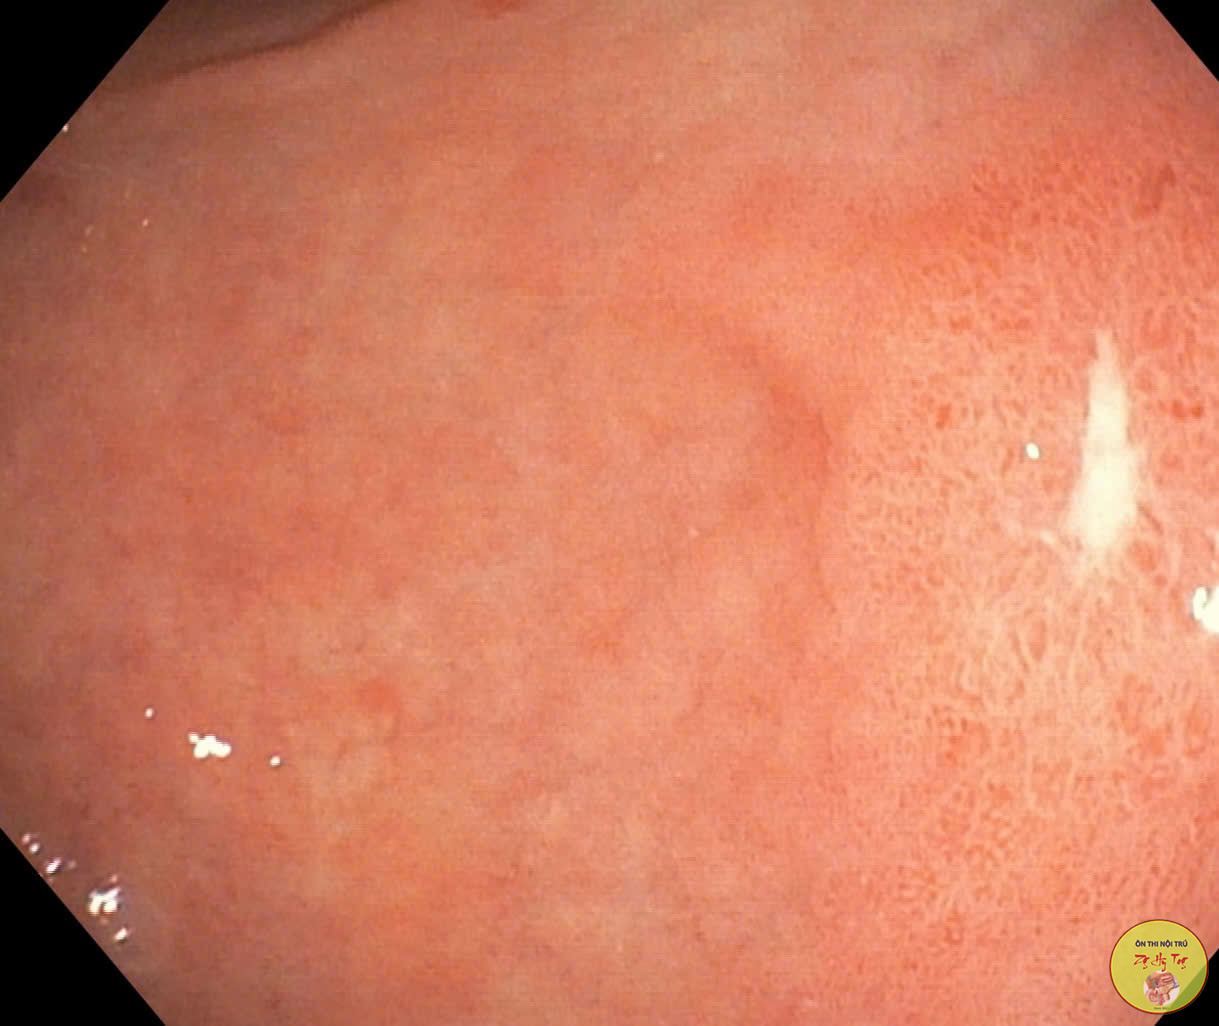

Ca lâm sàng thực tế, vận dụng lý thuyết bệnh học